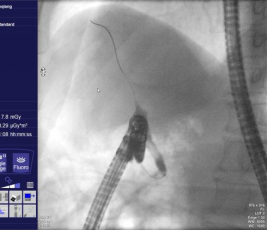

十二指肠乳头藏匿“隐秘角落” ,多发憩室让取石之路“荆棘丛生”,意味着这是一台高难度ERCP,面对这一复杂情况,黄华丽主任凭借其10余年丰富的ERCP实战经验,决定迎难而上,为患者实施ERCP取石术。术前黄华丽主任带领团队对患者的病情进行了复盘分析,鉴于传统手术取石风险较高,内镜微创手术伤害小,因此决定冒险采用ERCP取石术。充分沟通手术的必要性及十二指肠降部解剖结构异常导致手术难度,制定了详细的手术方案,并对手术过程中可能出现的各种情况进行了充分的预判和应对准备。患者及家属果断同意行ERCP术。术中,黄华丽主任通过巧妙调整内镜角度、最终找到藏匿在憩室旁边被挤压的十二指肠乳头,因结构异常只能长镜身插管,成功插管进行造影以明确结石的位置、大小和数量,取石球囊反复取石,成功将患者胆总管内的结石一一取出(见图2、3、4、5)。整个取石过程顺利,未出现明显并发症。患者术后恢复情况良好,未出现明显的疼痛和不适。患者术后腹痛、发热症状完全消失,黄疸逐渐消退。

图2 胆总管插管

图3 造影显示胆总管内结石负影